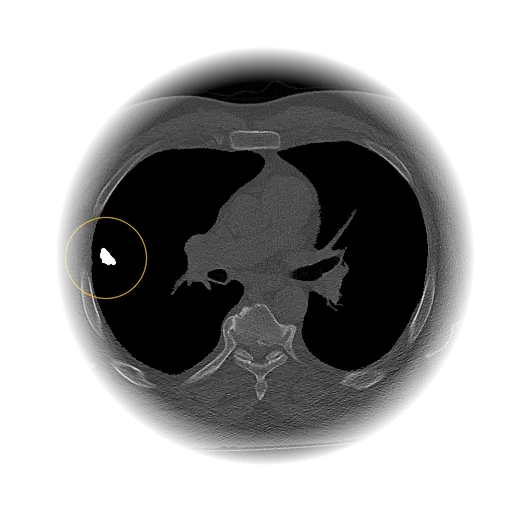

Lung Nodule Detection and Tracing Across Scans

Obvios.ai utilizes cutting-edge artificial intelligence to meticulously detect and track lung nodules, facilitating swift and precise diagnostics, thereby ensuring superior care and timely intervention for patients.